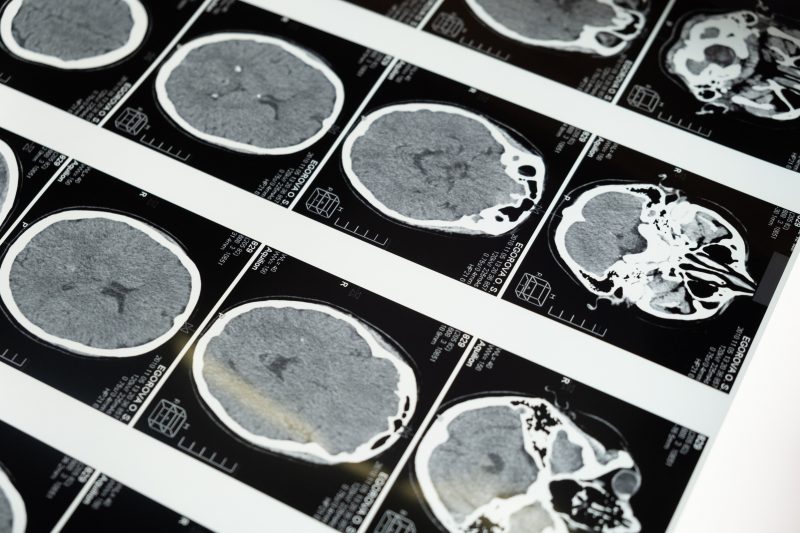

Tomografia de crânio de paciente com esclerose múltiplaDoença afeta pessoas jovens e é mais comum em mulheres – Foto: Pexels/Divulgação/ND

A esclerose múltipla é uma das doenças mais comuns do sistema nervoso central e afeta principalmente o cérebro, a medula espinhal e os nervos ópticos. O transtorno é crônico e autoimune, ou seja, as células de defesa atacam o próprio sistema nervoso central.